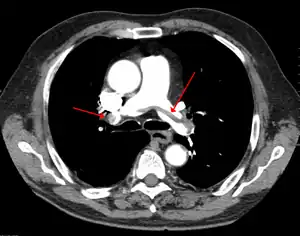

Chest spiral CT scan with radiocontrast agent showing multiple filling defects both at the bifurcation ("saddle" pulmonary embolism) and in the pulmonary arteries

CT angiography

CT pulmonary angiography (CTPA) is a pulmonary angiogram obtained using computed tomography (CT) with radiocontrast rather than right heart catheterization. Its advantages are that it is accurate, it is non-invasive, it is more often available, and it may identifying other lung disorders in case there is no pulmonary embolism. The accuracy and non-invasive nature of CTPA also make it advantageous for people who are pregnant.[51]

Large saddle embolus seen in the pulmonary artery (white arrows).